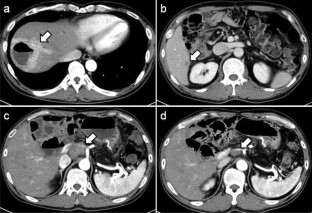

We report a case of a male in his 50 s who underwent pancreaticoduodenectomy for solid pseudopapillary neoplasm (SPN) of the pancreas at 30 years. He developed a liver abscess 15 years after the surgery, and CT scan revealed a swollen retroperitoneum lymph node and a tumor in the liver. Symptoms, including abdominal distension, appetite loss, and epigastric pain, appeared due to lymph node metastasis. Endoscopic ultrasonography-guided fine-needle aspiration against the lymph node revealed SPN recurrence. The tumor had invaded the common hepatic artery, and surgery was not indicated. Chemotherapy of Gemcitabine/nab-Paclitaxel biweekly was performed 8 times; however, no reduction in tumor size was observed, and the patient’s symptoms worsened. Proton beam therapy (67.5 GyE in 25 fractions) was subsequently performed for lymph node metastasis, and led to a gradual reduction in lymph node metastasis, and an improvement in symptoms. No re-expansion of lymph node metastasis has been observed 3 years after proton beam therapy. Since SPN is low malignancy and most cases can be expected to be cured by surgery, there is currently no standard treatment of unresectable SPN. This case is the first report of proton beam therapy for SPN, and was considered to be effective.

Fig. 2